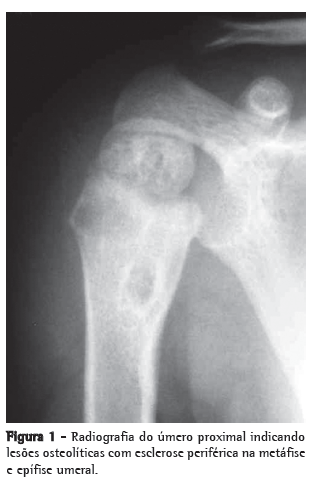

Menino de 21 meses, nascido em São Paulo, foi atendido com febre e leve comprometimento funcional do membro superior direito. A criança apresentava episódios de febre diária (acima de 38°C), predominantemente noturna. Uma semana antes da consulta, tinha iniciado com dor à palpação e à movimentação, bem como limitação de movimento do braço direito. A mãe negava história de trauma local. A radiografia do membro superior direito mostrou lesões osteolíticas na epífise e metáfise proximais umerais com bordas mal definidas, circundadas por áreas de esclerose óssea reativa, reação periosteal e aumento de partes moles (Figura 1). A ressonância magnética mostrou áreas de sinal medular anormal e edema de tecidos moles com realce pelo meio de contraste da medula infectada, sinais compatíveis com osteomielite no úmero proximal (Figura 2). O paciente recebeu cefalosporina por 10 dias em regime ambulatorial. No oitavo dia de antibioticoterapia, a criança veio a nosso serviço em virtude da febre e dor persistente.

A radiografia mostra lesões líticas com halo esclerótico, reação periosteal e osteoporose periarticular.(4,9-11) O estudo histopatológico mostra inflamação granulomatosa com células epitelioides, com ou sem necrose caseosa. Bacilos álcool-ácido resistentes são detectados em cerca de metade dos casos, e a maioria apresenta reação forte para PPD.(9,12)

Lesões líticas e escleróticas ósseas com reação periosteal caracterizam as lesões radiográficas. Os achados de TC na epífise, na metáfise e na diáfise foram consistentes com a descrição prévia em pacientes jovens.